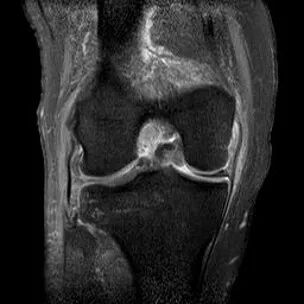

桶柄状撕裂MRI表现

1、宽度减小,在通过半月板体部的冠状面上蝶形消失,同时可见内移的半月板位于髁间窝、交叉韧带旁2、矢状面示残余的前角或后角变小或截断3、半月板前(后)角增宽或双半月板前(后)角征4、双前交叉韧带或双后交叉韧带征

桶柄状撕裂(双后交叉韧带征)

桶柄状撕裂:双前交叉韧带征